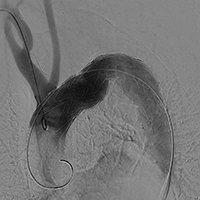

■胸部大動脈瘤におけるステントグラフト内挿術

TEVAR術中画像(1) |